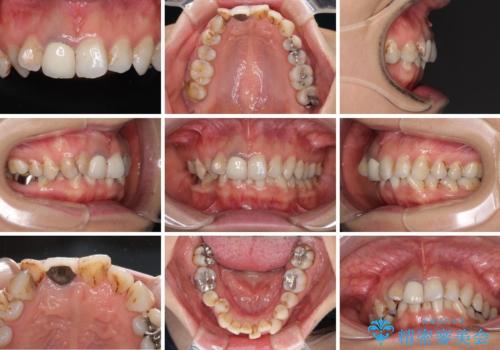

- 前歯の歯並びやむし歯治療の跡、奥歯の銀歯を気にして来院された患者様です。

インビザラインによる矯正治療の後に虫歯や銀歯をセラミックにて補綴することとしました。

前歯のむし歯治療の跡や奥歯の目立つ銀歯がなくなり、明るい口元になりました。